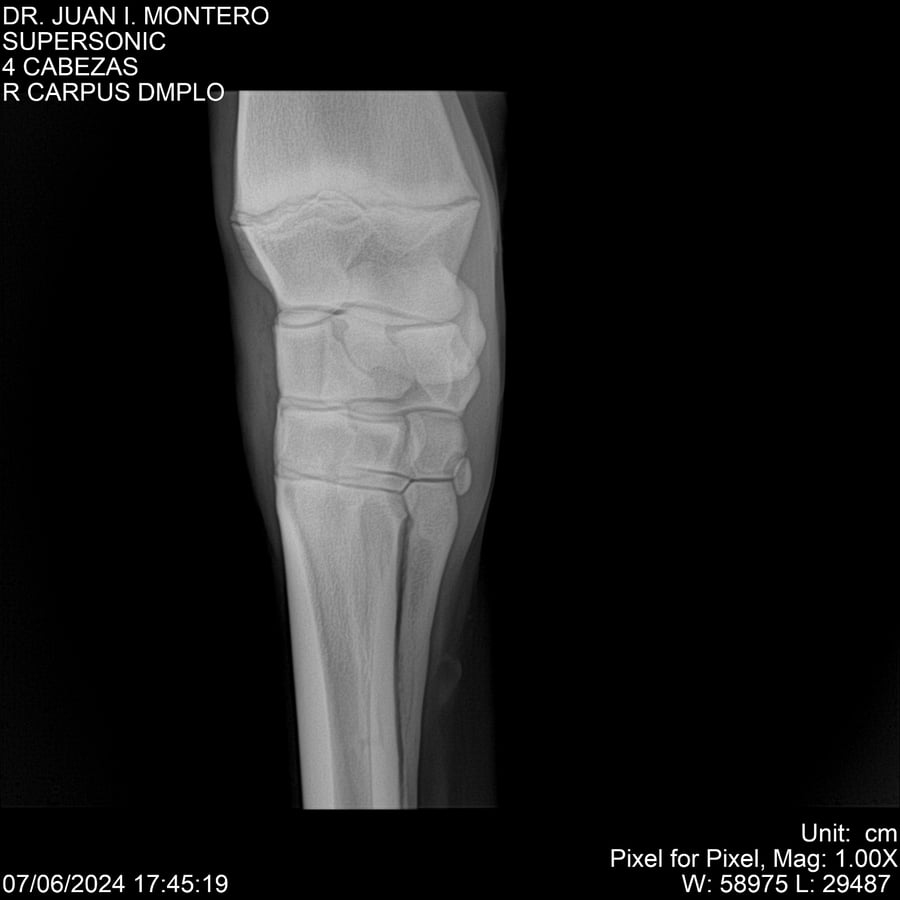

LOTE 5, SUPER SONIC Lote Anterior Volver al remate Lote Siguiente Ficha Contacto Montevideo - Ficha del Lote Identificador: #281089 Categoría: Yeguarizos Montevideo - 69 Visualizaciones ClicData Contacto Empresa: Abelenda N. R., Walter Hugo Nombre*: Teléfono* : E-mail* : Mensaje Enviar Registrese gratis Este contenido Exclusivo está disponible sólo para usuarios registrados Ingresar